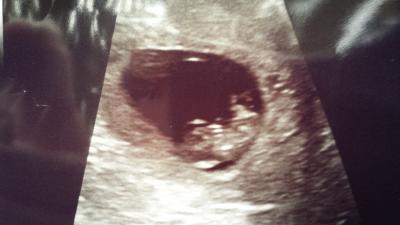

Ich darf präsentieren - das 1. "Foto" unseres Krümels *schmacht* Alles bestens! Herzchen schlägt und Krümel bewegt sich. Bin heute 9+2 aber laut US schon 9+4. FA korrigiert aber nicht, da ich ja weiss wann ES und GV war. Hab Magnesium verschrieben bekommen gegen die Kopfschmerzen im Zusammenhang mit dem Erbrechen. Wegen Erbrechen habe ich nun ein Dauerrezept für Tablette und Zäpfchen. FA ist aber guter Dinge dass es mit der 13. SSW wieder gut ist, da es relativ spät angefangen hat. Mal sehen.....